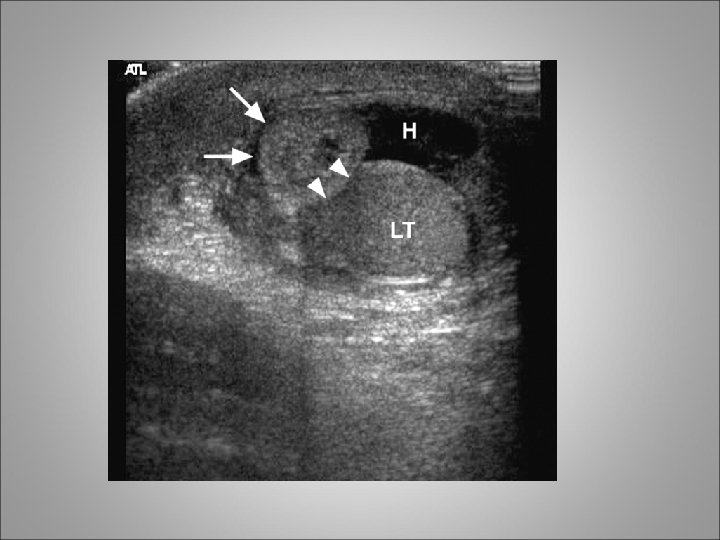

Testicular Trauma • Testicular rupture or fractured testis refers to a rip or tear in the tunica albuginea resulting in extrusion of the testicular contents • Blunt trauma accounts for approximately 85% of cases, and penetrating trauma accounts for 15% • As many as 80% of hematoceles (blood in the tunica vaginalis) are associated with testicular rupture

Clinical diagnosis • Patients typically present to ER with a straightforward history of injury • Symptoms include extreme scrotal pain, frequently associated with nausea and vomiting • Physical examination often reveals a swollen, severely tender testicle with a visible hematoma • Scrotal or perineal ecchymosis may be present • When evaluating a patient with a clinical history of only minor trauma, do not overlook the possibility of testicular torsion or epididymitis

Clinical diagnosis • For penetrating injuries, determine the entrance and exit sites of the wound. • Screening urinalysis is important to rule out urinary tract infection or epididymo-orchitis • Scrotal ultrasound imaging with Doppler studies is valuable for diagnosing and staging testicular injuries • The presence of a disrupted tunica albuginea is pathognomonic for testicular rupture

Indications for scrotal exploration • Uncertainty in diagnosis after appropriate clinical and radiographic evaluations • Disruption of the tunica albuginea • Large hematocele • Absence of blood flow on scrotal ultrasound images with Doppler studies

scrotal exploration • Clinical hematoceles that are expanding or of considerable size (eg, 5 cm or larger) should be explored • Collections of smaller size are also often explored, because it has been shown that such practice allows for more optimal pain control and shorter hospital stays • If the testis is fractured, testicular debridement and surgical closure of the tunica albuginea are necessary